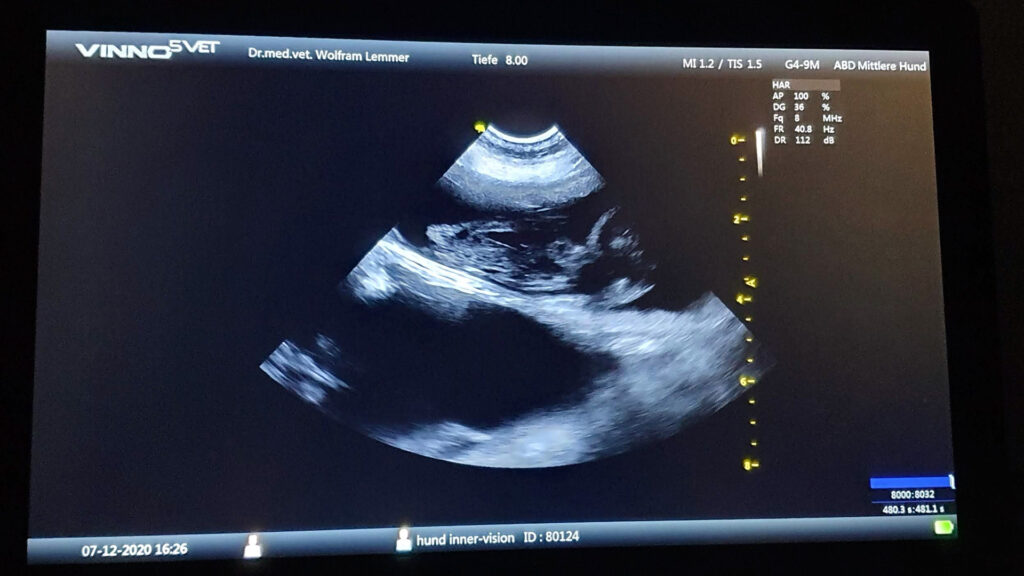

The echo scan showed it clearly: Opra (BISS Ch Inner Vision Wolfblood) is pregnant, five or six babies sired by Tio (Benedictus of Kahnawake), are growing nicely. With everything going smoothly, the puppies of litter F will be born around New Years Eve. We are really thrilled to welcome these […]